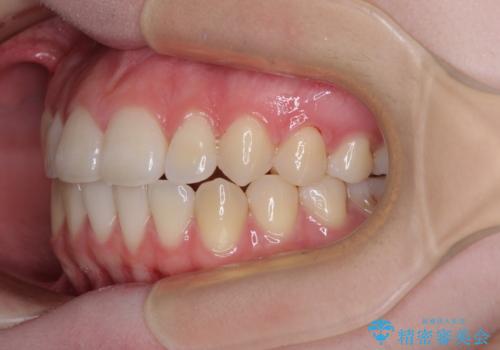

カリエール・ディスタライザーとインビザラインを用いた八重歯の改善

- 前歯の叢生と上顎左右の八重歯を気にして来院された患者様です。

奥歯の咬み合わせを見ると、左側は上顎が下顎に対して相対的に前方にあり、上下の前歯が接触していない状態でした。

咬み合わせを改善するためには、左側上顎臼歯を後方に移動させた咬み合わせにする必要があります。

インビザライン単体で改善することも可能性もありますが、インビザライン単体で達成する可能性が低いと考えられたため、カリエール・ディスタライザーという補助装置を併用して、より確実性を上げることとしました。

奥歯の咬み合わせを改善しながら、並行してインビザラインで歯列を整えることとしました。

カリエールディスタライザーを併用したことで、左側臼歯の咬み合わせを確実に改善させることができました。